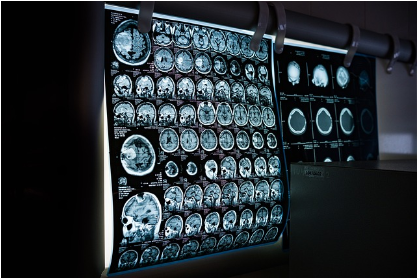

2. 영상 검사

1) 초음파 검사: 혈류와 정맥의 상태를 평가합니다.

2) CT 스캔 또는 MRI: 더 정확한 진단을 위해 사용될 수 있습니다.